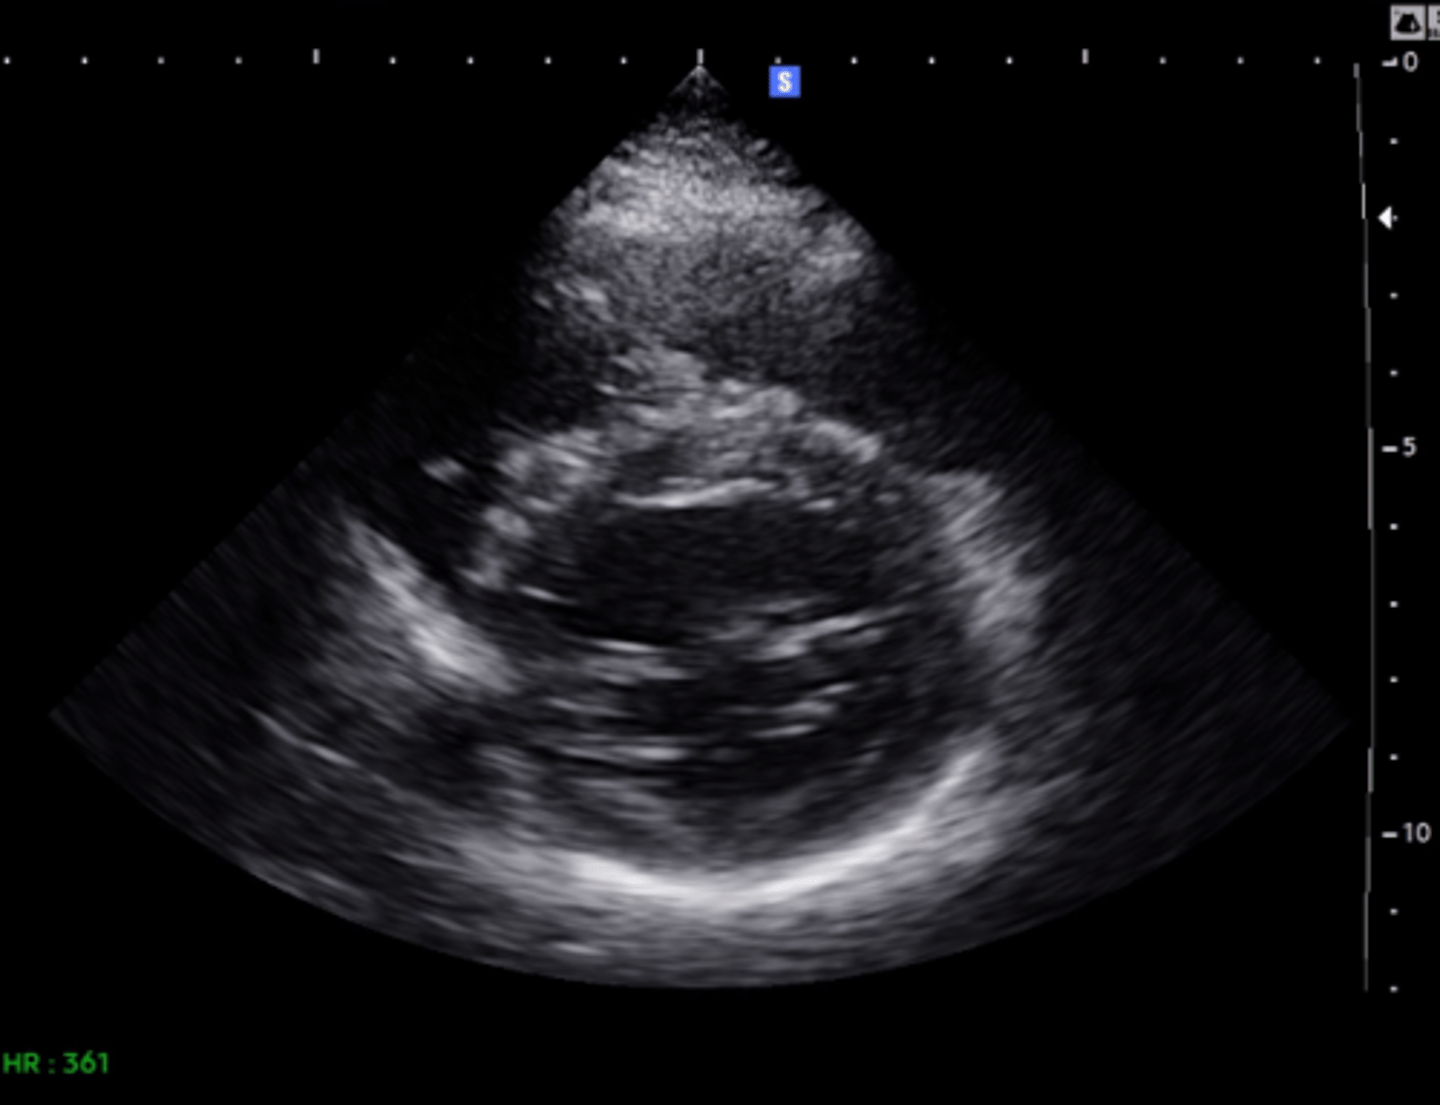

MV PLAX (top leaflet)

AMVL

MV PLAX (bottom leaflet)

PMVL